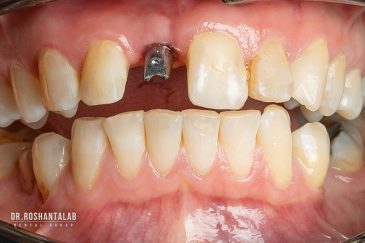

دندانپزشکی زیبایی

طراحی لبخند هالیوودی با متدهای لمینت سرامیکی دندان و کامپوزیت ونیر در کنار اصلاح فرم، خدمات بلیچینگ و روکش دندان، زیبایی چهره شما را تکمیل میکند.ترمیم دندان

تجربه کاشت دندان دیجیتال و بدون درد در ۳ دقیقه! استفاده از برترین برندها زیر نظر جراح، با هزینه مناسب و خدمات کامل از کاشت دندان تا روکشارتودنسی دندان

انتخاب بهترین متخصص ایمپلنت که به تکنیکهای روز دنیا مسلط باشد، تضمینکننده سلامت فک و زیبایی لبخند شماست. در کلینیک دندانپزشکی دکتر روشنطلب، ما با بهرهگیری از تجهیزات دیجیتال در ۵ شعبه فعال (تهران، اصفهان، رشت و استانبول ترکیه)، خدمات تخصصی کاشت ایمپلنت دندان را برای بیمارانی که کیفیت و دقت برایشان اولویت دارد، ارائه میدهیم. در این متد، پروسه درمان با ظرافت بالا انجام شده؛ راهکاری ایدهآل برای کسانی که به دنبال درمان بدون درد با بالاترین نرخ موفقیت هستند.